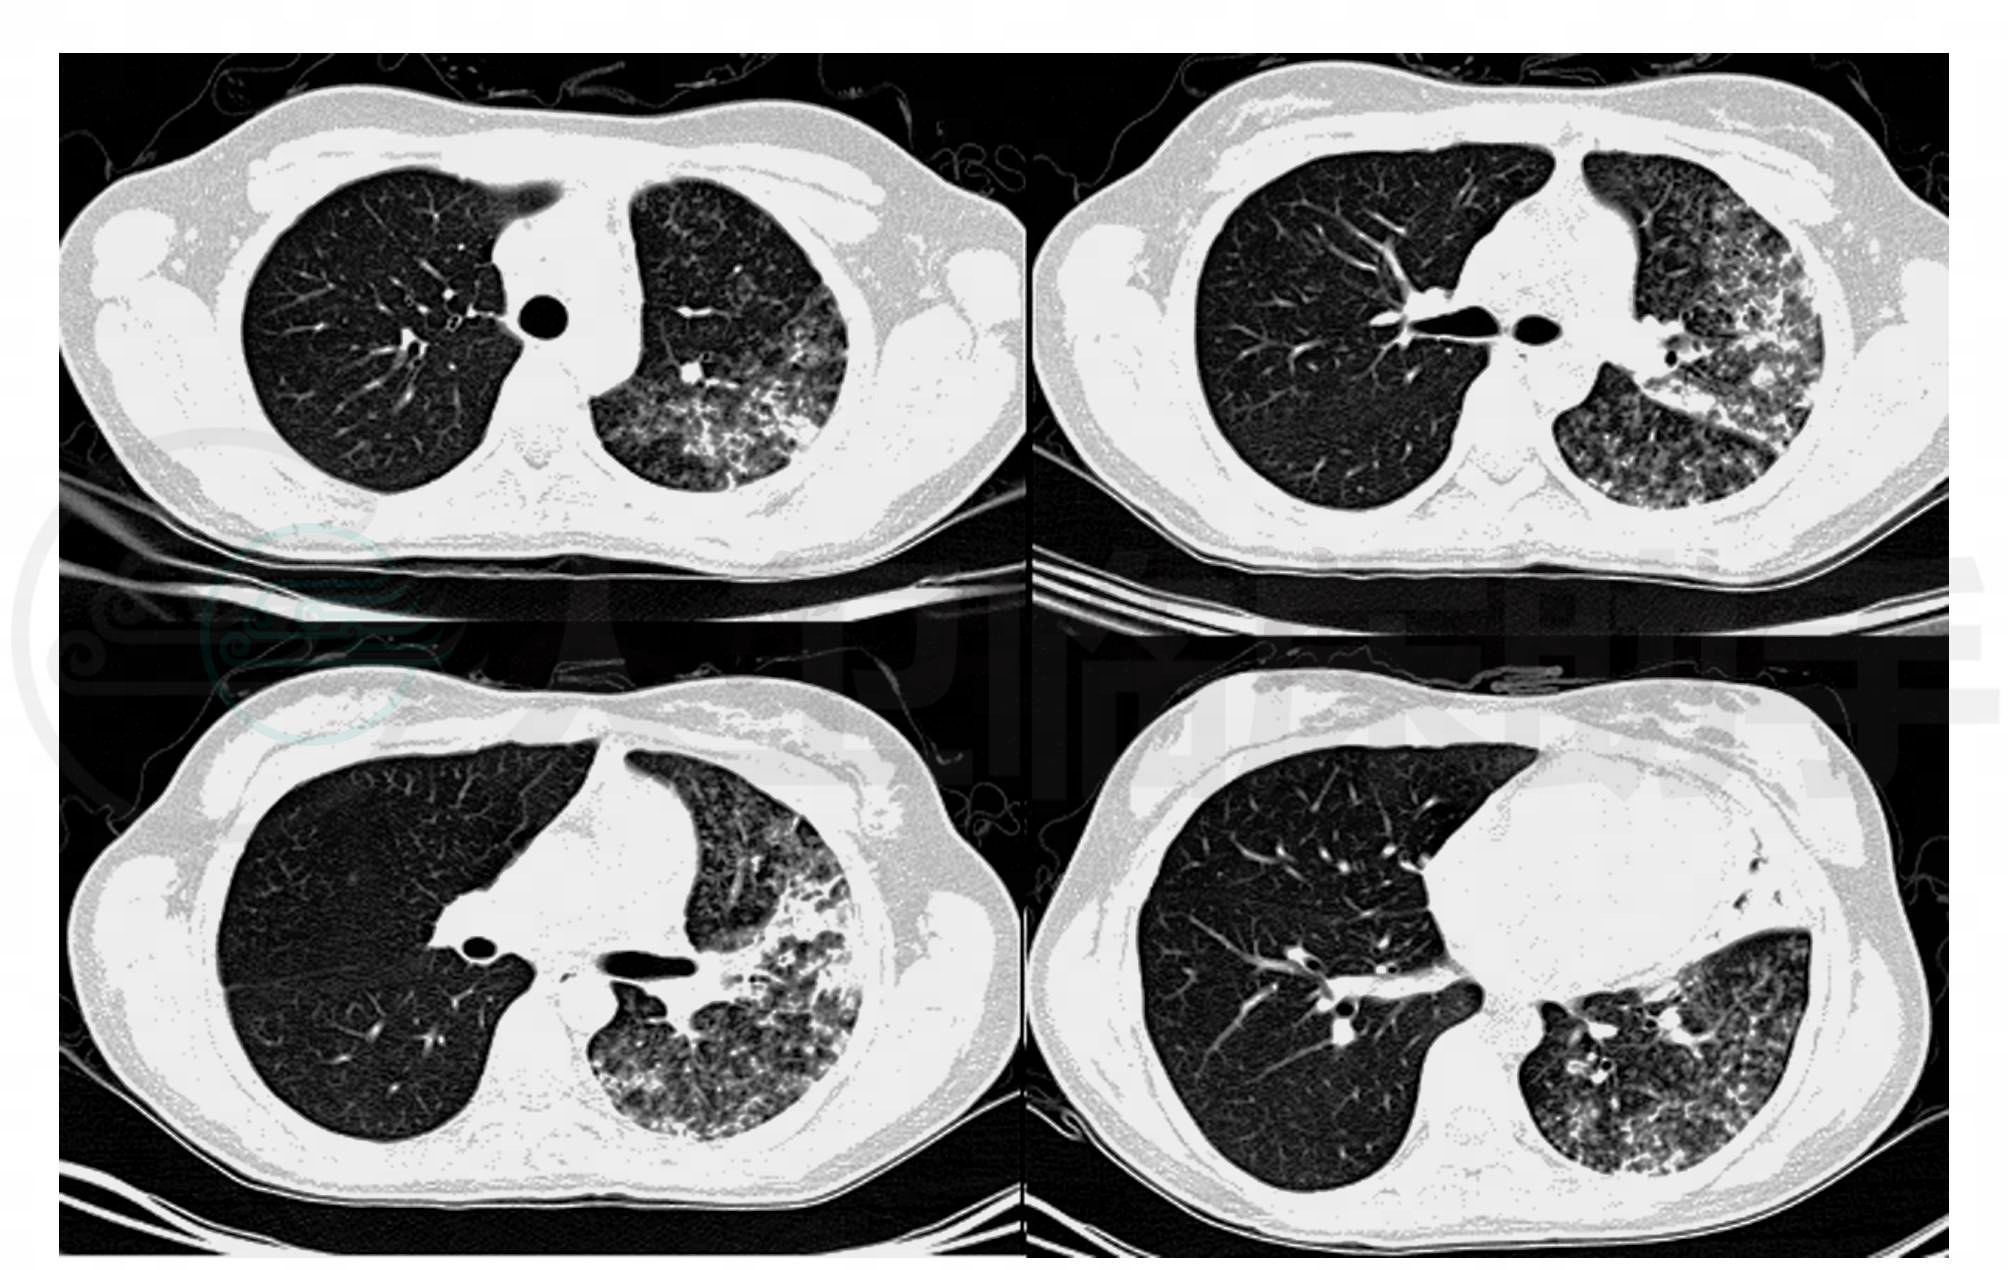

2008年11月3日,患者再次入院。查体没有明显阳性体征发现。辅助检查:2008年10月29日血常规:WBC:10.2×109/L,NE%:64.10%,RBC:4.25×1012/L,HB:126g/L,PLT:257×109/L;肺CT:左肺感染性病变,较前未见好转,左肺病变合并多发空腔(肺气囊?)或空洞形成(图4)。治疗给予万古霉素,应用3天。患者体温及咳嗽症状没有明显改善。建议患者抗结核治疗,半月后体温正常,规范治疗半年,停药,未再发。

图4 2008年10月29日